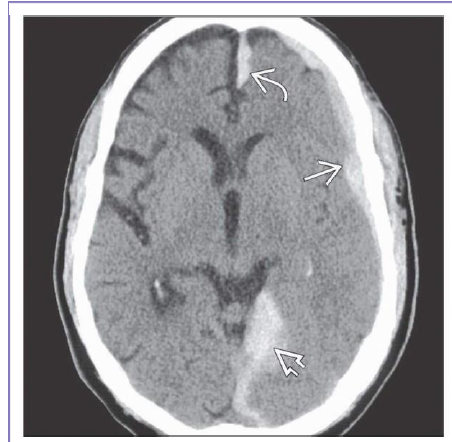

What structures have been affected in this pt with SDH?

Acute SDH spreads over left hemisphere , along tentorium , into interhemispheric fissure but does not cross midline.